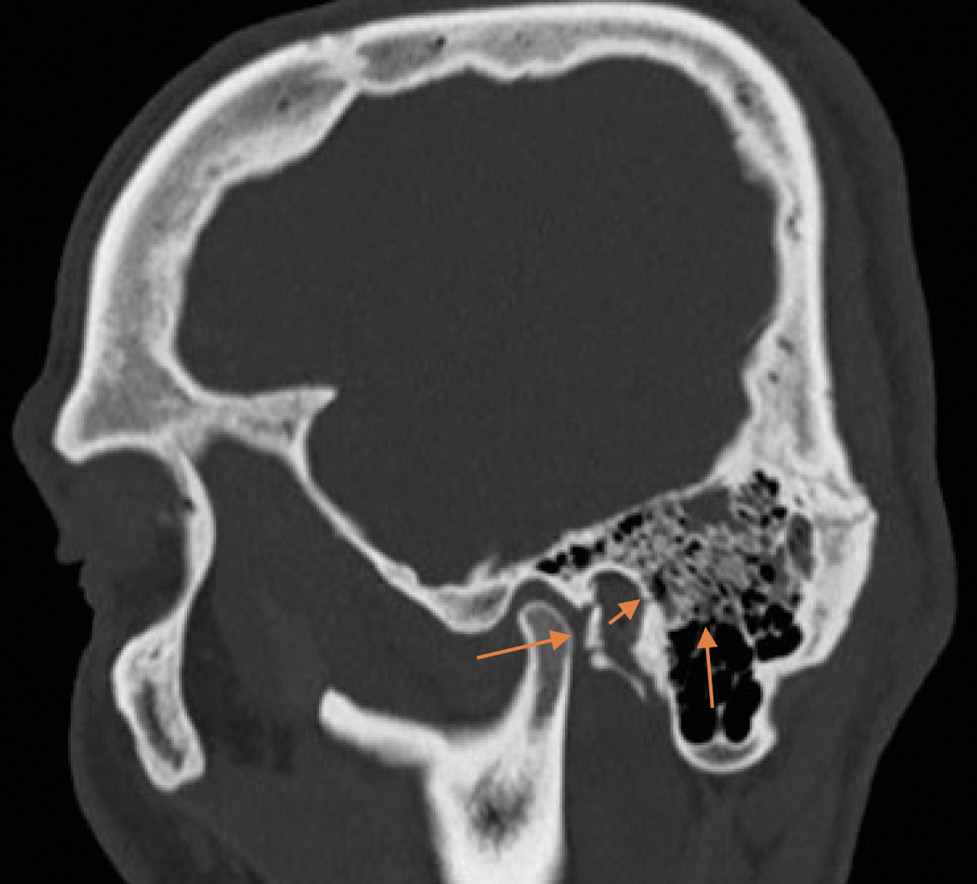

На экспертизу дополнительно представлены результаты мультиспиральной компьютерной томографии головного мозга гражданина Л., благодаря которым экспертом выявлено следующее. На серии компьютерных томограмм (с последующим 3D-моделированием) в лобно-височно-теменной области слева субдуральная гематома максимальной толщиной до 4 мм. В полюсно-базальных отделах левой височной доли определяются мелкие очаги геморрагической плотности, местами сливного характера (рис. 1, 2). Боковые желудочки симметричные. Срединные структуры мозга не смещены. Субарахноидальное пространство нивелировано слева. В бороздах мозга левой височной, левой теменной долей геморрагическое содержимое (субарахноидальное кровоизлияние), малая эпидуральная гематома правой теменно-височной области. Перелом сосцевидного отростка правой височной кости: линия перелома распространяется на пирамиду правой височной кости и заднюю стенку наружного слухового прохода (рис. 3–5). Наличие геморрагического содержимого в ячейках правого сосцевидного отростка, в антруме справа и в правой барабанной полости.

Рис. 4. Мультиспиральная компьютерная томография головного мозга: перелом пирамиды правой височной кости с переходом на заднюю стенку наружного слухового прохода и кровоизлияние в ячейки сосцевидного отростка, в антрум, барабанную полость справа (стрелки) на сагиттальном срезе.